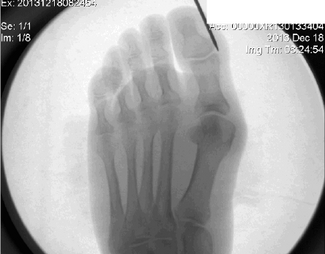

bunion

Conference Coverage

07/13/2023

Brian McCurdy

Panelists at the APMA National forefoot track discussed iatrogenic forefoot deformities, the evolution of bunion surgery, osteochondral lesions of the talus, and first MTPJ arthrodesis.